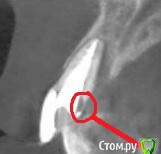

Евгений Ходыкин Опубликовано 7 декабря, 2018 Поделиться Опубликовано 7 декабря, 2018 Всем привет! Зуб 2.1. Подозрения на трещину. Основной очаг деструкции сосредоточен нёбно. Высоту потери стенки видно на срезе. У кого какие варианты реабилитации? Ссылка на комментарий

Дмитрий Л. Опубликовано 7 декабря, 2018 Поделиться Опубликовано 7 декабря, 2018 Так есть трещина или нет? У трещины специфическая симптоматика. Может там латераль канала. Хлорочкой помыть, кальция положить.Проверьте на витальность 22. Что это на снимке? Перфа, резорбция? Ссылка на комментарий

Евгений Ходыкин Опубликовано 7 декабря, 2018 Автор Поделиться Опубликовано 7 декабря, 2018 Так есть трещина или нет? У трещины специфическая симптоматика. Может там латераль канала. Хлорочкой помыть, кальция положить.Проверьте на витальность 22. Что это на снимке? Перфа, резорбция? 2.2 жив. В крайнем эндо уверен, каналец бы вымылся точно. Насчёт того, что Вы увидели сказать однозначно не могу. Покручу ещё срезы) Ссылка на комментарий

Дмитрий Л. Опубликовано 7 декабря, 2018 Поделиться Опубликовано 7 декабря, 2018 Более информативно будет отодвинуть край десны и заглянуть либо распломбировать канал коронально и посмотреть что там. Если правда резорбция или перфа, то закрыть какой-то МТАшкой, понаблюдать полгода минимум, кость может восстановиться и даже если жалобы снова появятся то имплантация будет в более благоприятных условиях. Ну это моё мнение Ссылка на комментарий

Дмитрий Л. Опубликовано 7 декабря, 2018 Поделиться Опубликовано 7 декабря, 2018 Ну не знаю. Инвазивная цервикальная резорбция. Почитайте. Не всё так радужно) Ссылка на комментарий

Alexey Doc Опубликовано 7 декабря, 2018 Поделиться Опубликовано 7 декабря, 2018 Опираясь только на данные КТ - показано удаление зуба. Одномоментная имплантация по возможности. Ссылка на комментарий

gum Опубликовано 8 декабря, 2018 Поделиться Опубликовано 8 декабря, 2018 Удаление и имплантация лучший вариант, или мостовидный протез.А в зубе культевая вкладка? Очень широкий канал. 11 похоже такой же Ссылка на комментарий